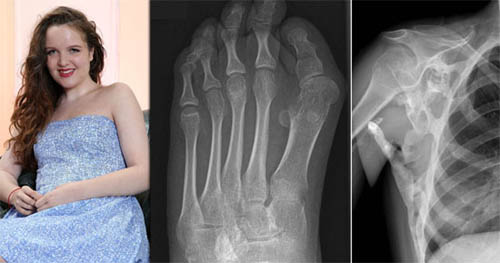

Bệnh lạ biến thiếu nữ thành "tượng sống"

Một chứng bệnh hiếm gặp về gene đang dần dần làm tê liệt toàn bộ cơ thể của một thiếu nữ xinh đẹp người Anh và rốt cuộc sẽ biến cô thành một pho tượng sống. Seanie Nammock, 17 tuổi, đến từ vùng Tây London, Anh đang phải chống chọi với căn bệnh FOP thường gọi nôm na là hội chứng "người hóa đá". Đây là dạng rối loạn đang biến các cơ và dây chằng của cô thành xương.

Cho tới này, bệnh đã tiến triển tới mức khiến các cánh tay của Nammock bị "khóa chặt" trong tư thế gập ngang eo, khiến chúng không thể cử động được. Việc phát triển thêm xương ở trên vai cũng khiến cô không thể nào với qua thắt lưng và luôn phải chật vật đánh răng, gội đầu hoặc mặc quần áo nếu không có sự trợ giúp. Tình trạng của Nammock được dự đoán có thể trở nên nghiêm trọng hơn. Bất kỳ va chạm nhỏ nhất nào cũng gây bùng nổ đau đớn, kích thích sự phát triển xương cột chặt các khớp của cô. Nammock hiện cũng không thể tiêm hay làm sinh thiết vì chúng có thể khiến xương hình thành ngoài ý muốn. Căn bệnh lạ còn khiến thiếu nữ xinh đẹp này dễ bị tai nạn hơn do khó túm vịn lan can cầu thang khi lên xuống và các cánh tay bất động ảnh hưởng tới khả năng thăng bằng của cơ thể. Thống kê cho thấy, hiện chỉ có khoảng 600 người trên thế giới được chẩn đoán mắc hội chứng FOP. Căn bệnh này hiện cũng vô phương cứu chữa. Bất chấp việc mắc chứng bệnh nan y, Nammock vẫn vui vẻ theo đuổi các đam mê của mình. Cô thích nấu ăn, đi mua sắm và vui chơi cùng bạn bè. Gia đình của Nammock đang cố gắng quyên góp gần 200.000 USD tiền ủng hộ để tài trợ cho một nhóm nghiên cứu về bệnh FOP ở Anh, với hy vọng họ sẽ tìm ra cách cứu mạng cô.